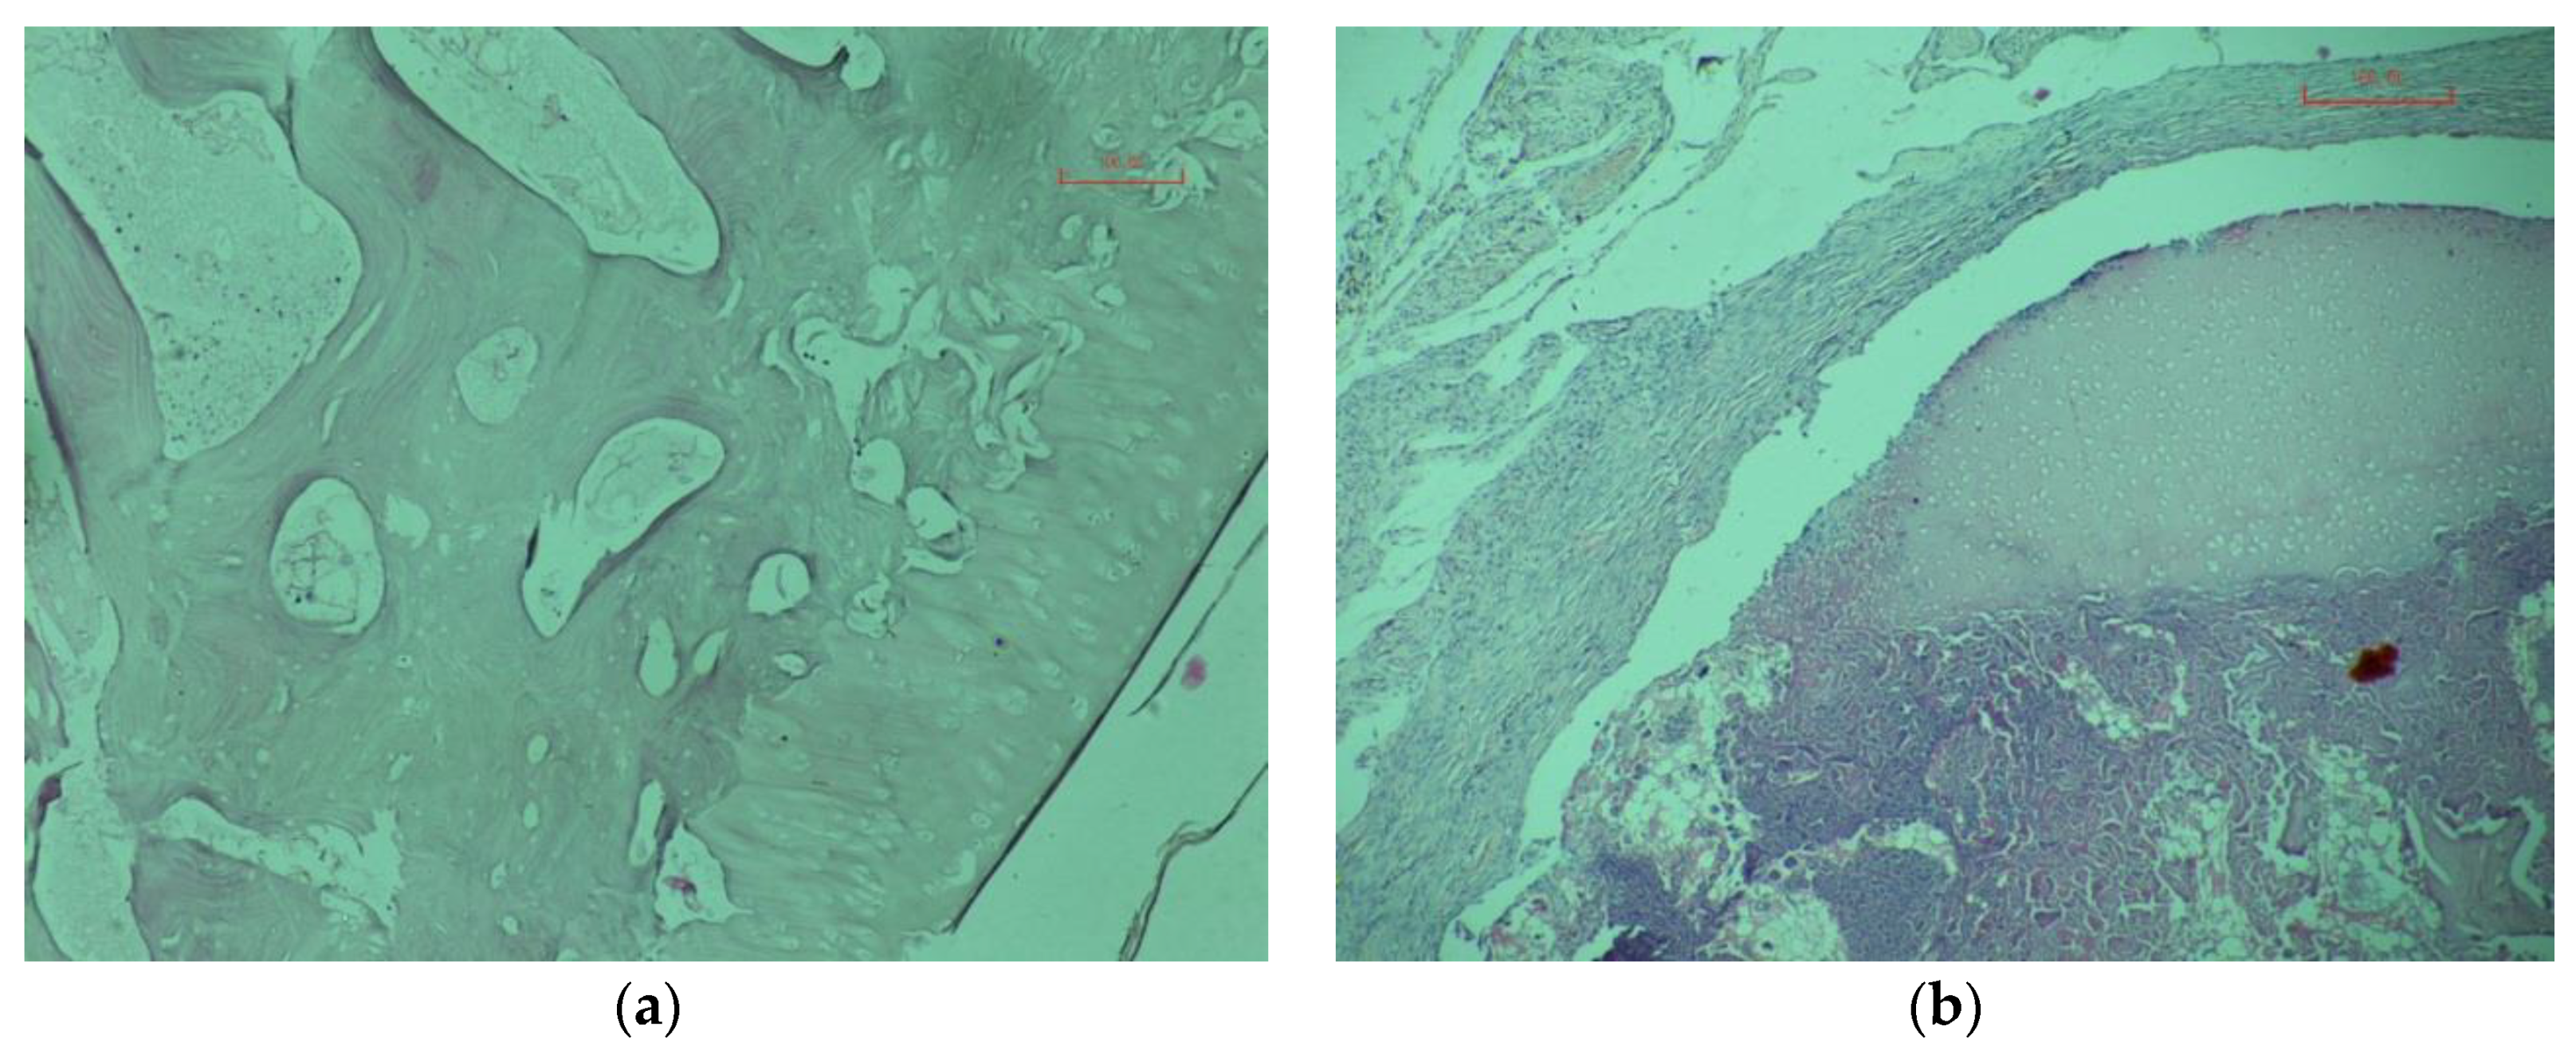

3.3. Manufacturing and Clinic Research